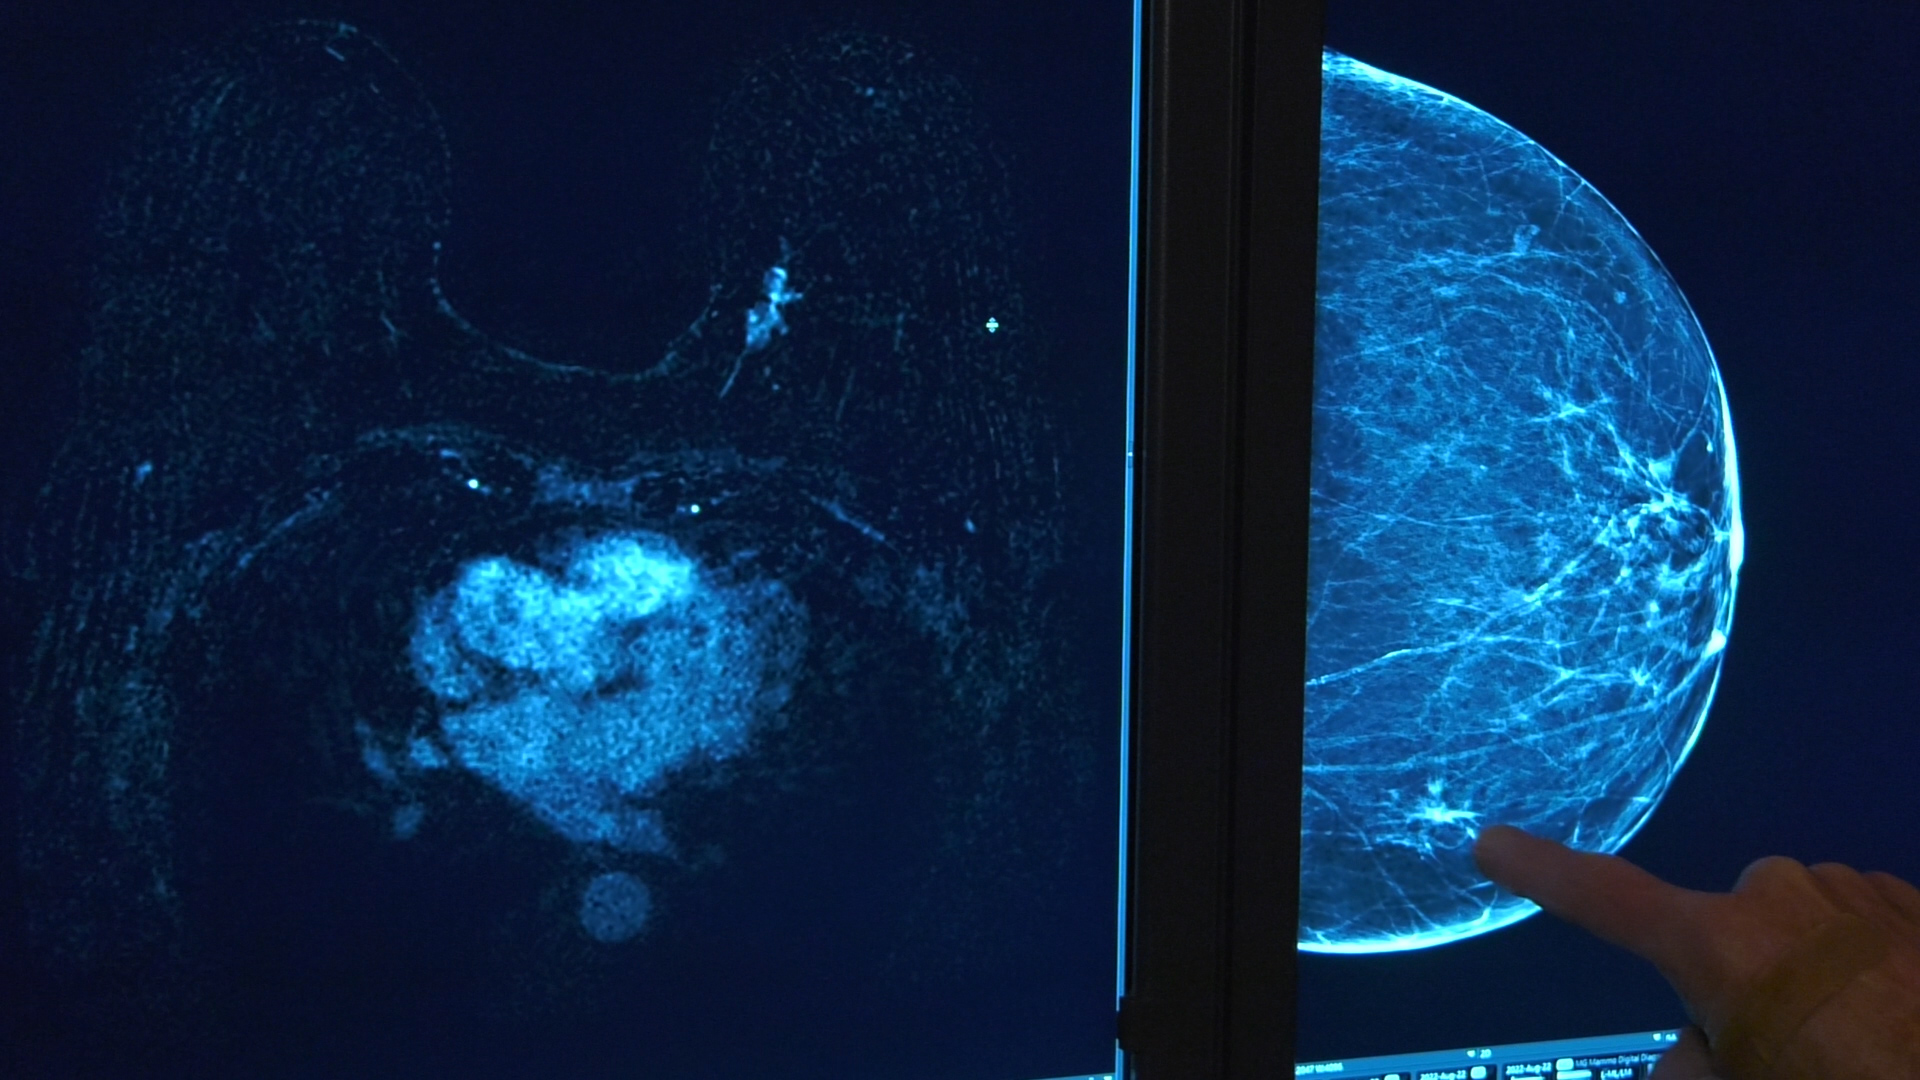

MURRAY — Intermountain Healthcare unveiled a new imaging tool for breast cancer screening for women who are at higher risk for breast cancer.

Dr. Brett Parkinson, the imaging director of breast care services for Intermountain Healthcare, said this new screening uses an MRI machine, a magnetic resonance imaging machine, to do a scan of just the breasts, rather than conventional MRI.

"It is the most powerful tool that we have in our armamentarium for the early detection of breast cancer," Parkinson said. "The MRI gives exquisite detail about breast tissue and anything that may be growing in the breast."